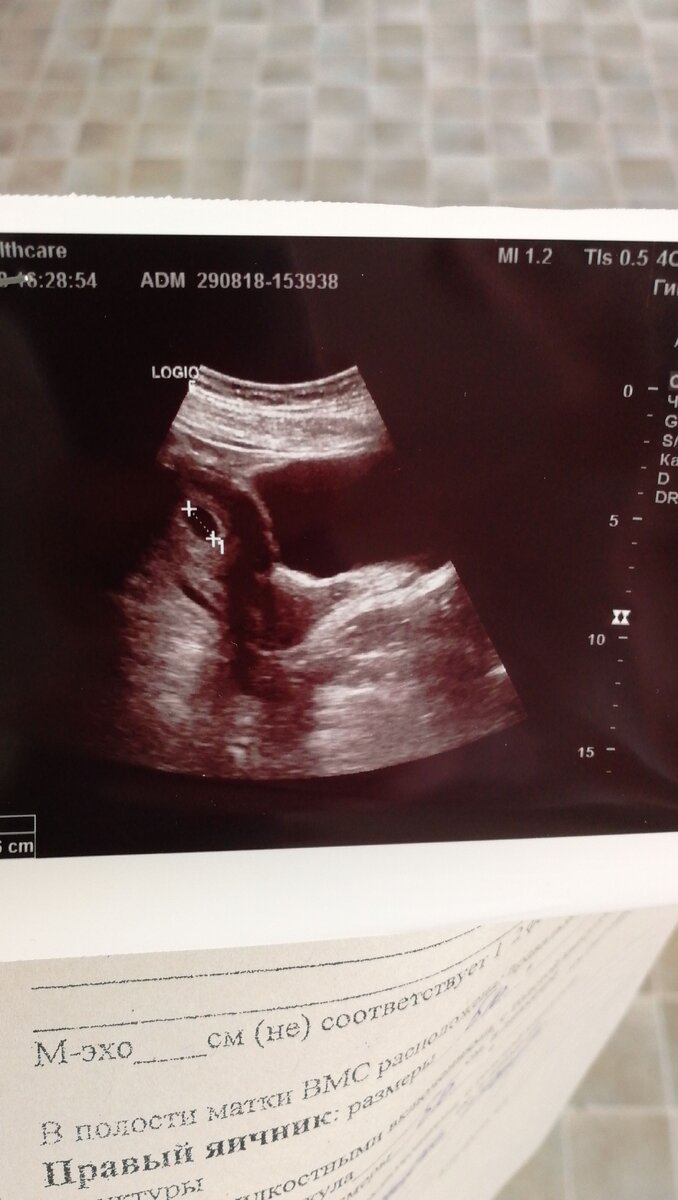

Знаете, как трудно бывает отказаться от хороших перспектив в пользу человечка, которого ещё и на свете-то нет? Я вот не знала до определённого момента... Да, возможно, многие из вас меня осудят - "дети - это счастье", "дал бог зайку, даст и лужайку" и т.д. Но у меня был чёткий план, которому я сделала. Я закончила университет, затем закончила интернатуру, уехала из своего региона в другой, получила хорошую должность, встретила будущего мужа. Далее у меня в планах было обзавестись семейным гнездышком, помочь маме с ипотекой. Ну а в перспективе когда - нибудь и дети. А тут - 2 полоски. Муж молчал весь вечер, я проревела всю ночь. К утру я твёрдо решила сделать аборт, потому что моя беременность была не по плану. Да и детей я не люблю. У меня обязательства перед мамой и т.д. Быстренько записалась к гинекологу, пошла на приём. Рассказала врачу, что принимаю АРВТ-препараты, прочитала про их тератогенное воздействие, что тест положительный, тошнит и рвёт постоянно. Меня посмотрели на кресле, подтвердили беременность в сроке 3-4 недели. Дали направление на УЗИ. Я спросила о прерывании, меня в ответ спросили о том, какая по счету беременность. Я ответила, что первая, мне сказали, что за неё следует побороться. Дали направление к генетику. Вот и все. До этого момента я надеялась, что тест врет. А оказалось нет. Пошла на УЗИ через неделю, беременность маточная, одиночная, срок 4-5 недель. Значит, оно растёт, то, что внутри... Решила серьёзно поговорить с мужем. Я была за прерывание, он против. Он подключил к нашему разговору свекровь, мою мать. В один голос они меня убежали, что стоит оставить малютку. Я под их натиском сдалась. Съездила к генетику, послушала возможные исходы моей беременности на фоне принятия АРВТ. И попыталась смириться.